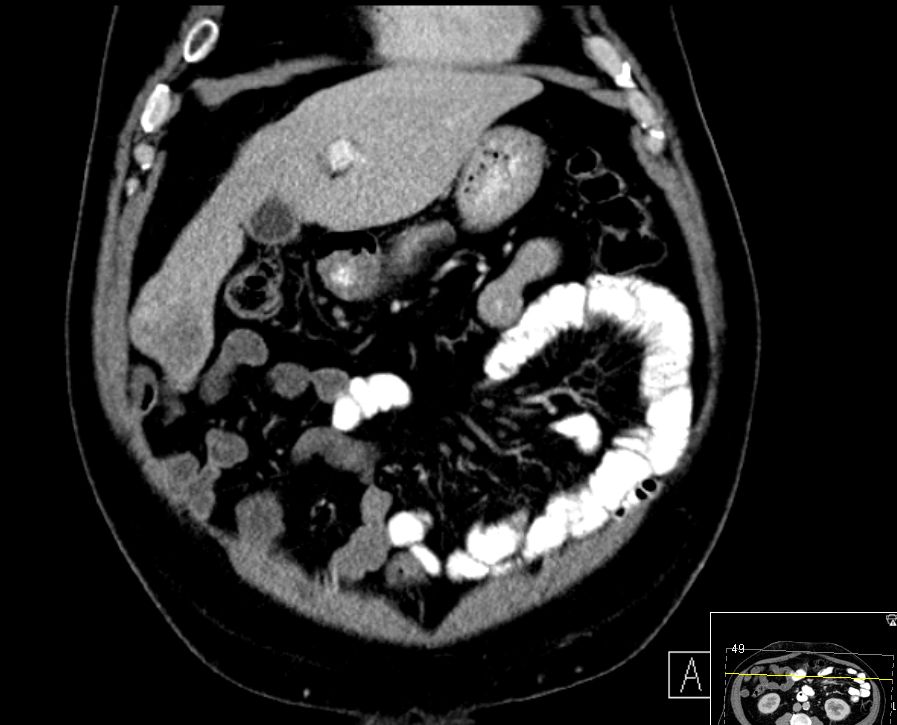

| intrahepatische Filiae | 68-jähriger Mann mit bekannter Leberzirrhose nach Alkoholabusus.

Im CT mehrere hypervaskuläre Herde gesehen.

Im MR beste Darstellung auf den Spätaufnahmen nach leberspezifischem Kontrastmittel in der hepatobiliären Ausscheidung.

Herd im Segment 4a unmittelbar am Gallenblasenbett 48mm.

![]() | |

Im 5. Segment subkapsulär rechts lateral ein 11mm großer, signalabgesenkter Leberherd.![]() |

Am Unterrand des rechten Leberlappens vom 6. zum 7. Lebersegment ein 17mm signalabgesenkter, subkapsulär gelegener Herd.![]() | ||